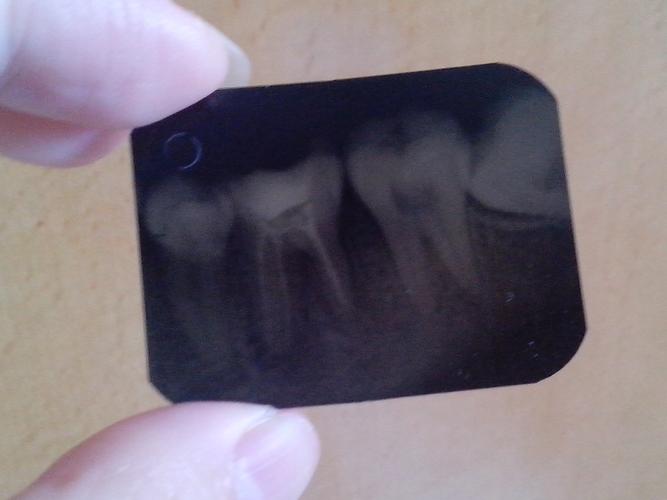

牙科小牙片机拍片技巧

小牙片

小牙片教程

口腔小牙片

小牙片技巧